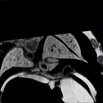

Caption Play MovieSerial 2D EFIC image stack in the coronal plane of 811-058-LB reveals dextrocardia, overriding aorta, and pmVSD